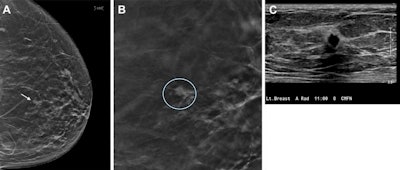

Digital breast tomosynthesis (DBT) increased breast cancer detection rates over a 10-year time period, researchers reported in a study published on 17 September in Radiology.

A group led by Dr. Liane Philpotts, from Yale University in New Haven, Connecticut, U.S., also found that DBT identifies invasive cancers with a lower rate of advanced cancers compared with digital mammography. The team added that this further improved on incident rounds of breast cancer screening.

The Yale team compared cancer types and stages with 10 years of DBT screening and over three years of digital mammography screening. It included data collected between 2008 and 2021 from 1,407 breast cancers. Of these, 1,265 were analyzed via DBT and 142 via mammography.

DBT led to a higher rate of cancer depiction than mammography (5.3 versus four cancers per 1,000; p = 0.001). The researchers added that DBT achieved a similar ratio of invasive cancers to ductal carcinomas in situ (DCIS) compared to mammography, at 76.5% versus 71.1%, respectively.

Among other findings, the modalities did not significantly differ in average invasive cancer size; both had similar rates of invasive cancer subtypes, and DBT had a lower proportion of advanced cancers.